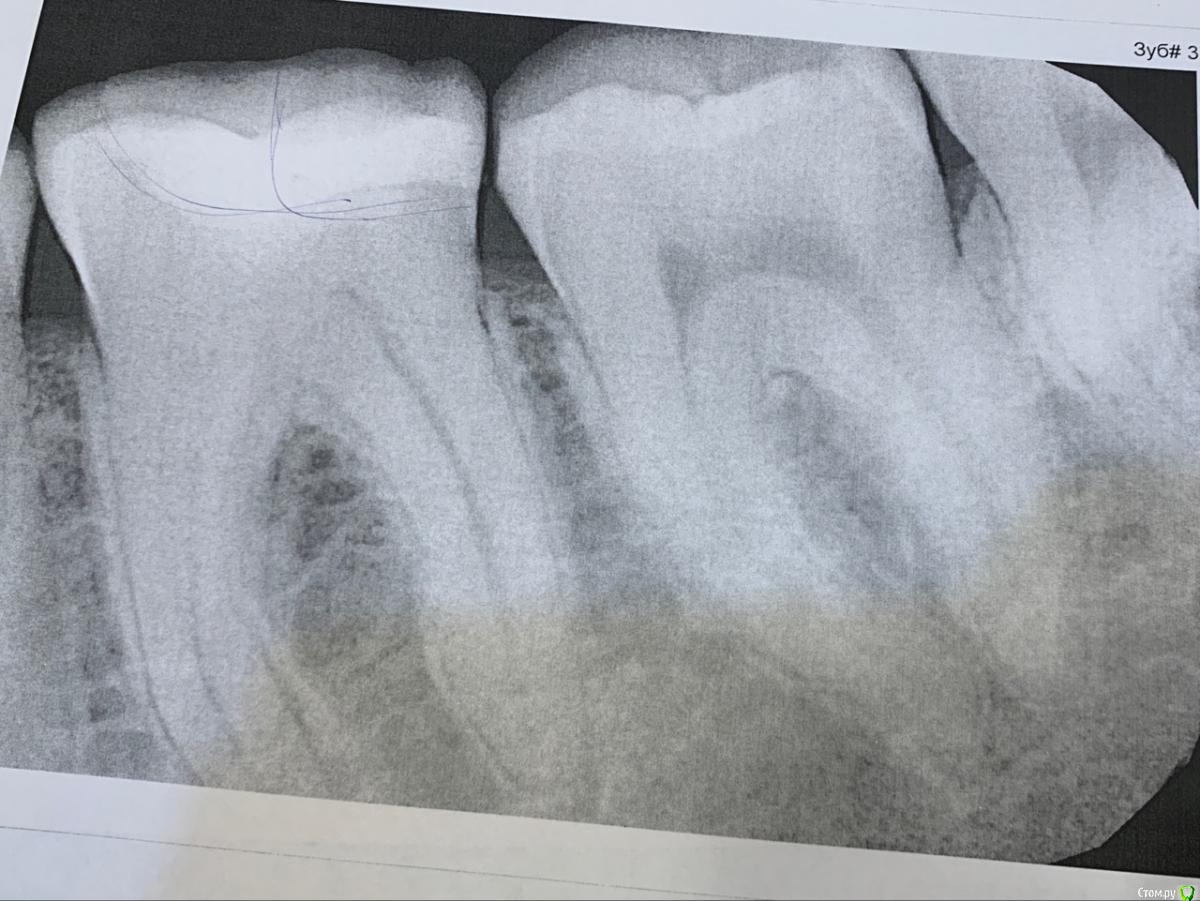

Lokox Опубликовано 16 августа, 2019 Поделиться Опубликовано 16 августа, 2019 (изменено) Добрый день уважаемые врачи!Начал болеть левый нижний жевательный зуб. Боли возникают только от горячей или сильно теплой еды/жидкости. Боль возникает и не проходит около 10 - 20 сек. На холодное/сладкое/ кислое - проблем нет. Зуб пломбированный.Обратился к стоматологу. Посмотрели зуб, постучали по нему, подули, побрызгали - боли никакой нет, сказали что на пульпит не похоже. Внешне сказали тоже все хорошо. Решили сделать рентген. Обнаружили что под пломбой трещина и кариес. Решили залечить. Пока лечили, сказали что кариес очень глубокий, но не пульпит. В итоге поставили пломбу, а зуб как болел от горячего так и болит Врачи сказали что может поболеть какое-то время. Прошло уже две недели, боль на горчее все еще естьПодскажите пожалуйста, сколько может еще болеть и норально ли это?Заранее спасибо Изменено 16 августа, 2019 пользователем Lokox Ссылка на комментарий

DmitrySH Опубликовано 20 августа, 2019 Поделиться Опубликовано 20 августа, 2019 Термопробы сделать и сравнить с другими зубами. Скорее всего нерв убирать Ссылка на комментарий